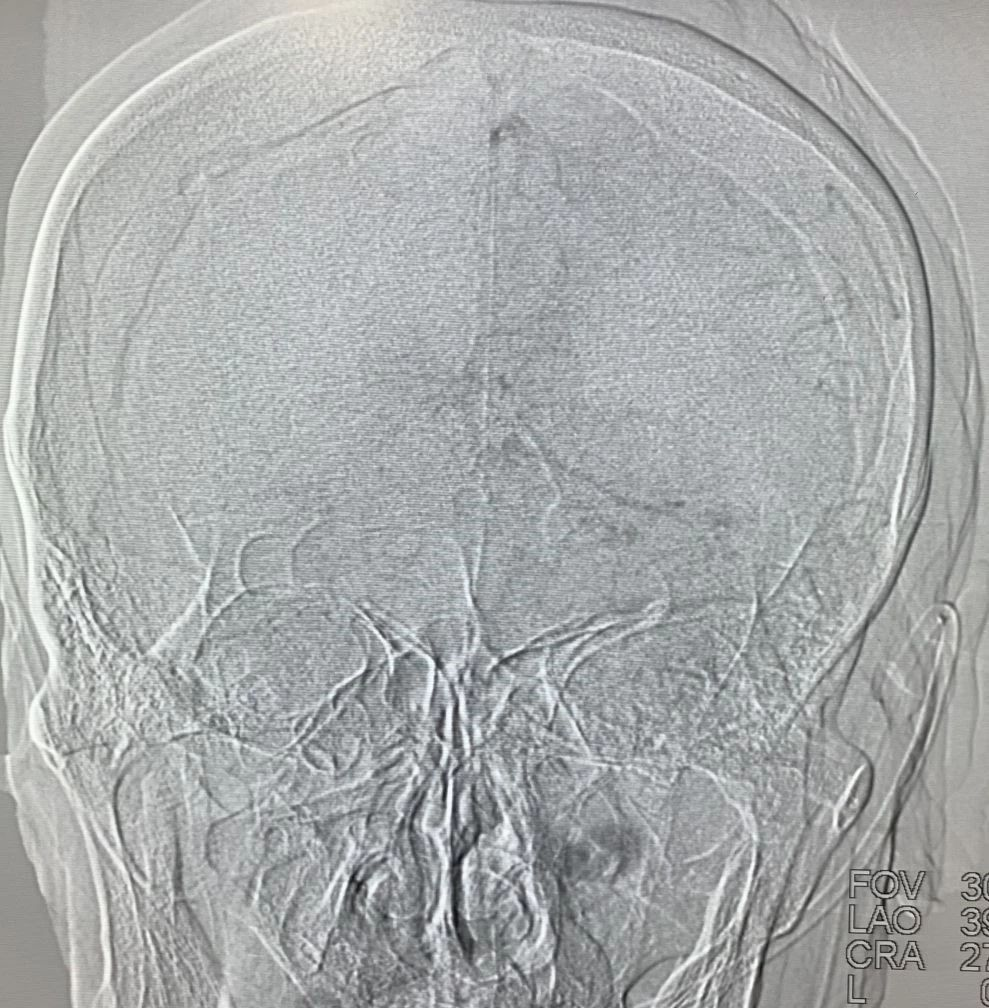

术后造影,mTICI分级III。

一、该患者血栓负荷较重,得益于加奇申翼®取栓器独特的前段“网兜”设计,经历2次取栓,但无明显血栓逃逸。此外,该产品还具有较长的工作长度和更大的网孔设计,良好的血栓嵌合能力以及优秀的抗折性和贴壁性,支架可以整体显影,并可以在内腔为0.017 inch的微导管输送。

三、目前两例使用加奇申翼®取栓器,病人均快速获得血管再通,其中第二例病人一次取栓则完全再通,两例病人均无明显并发症。